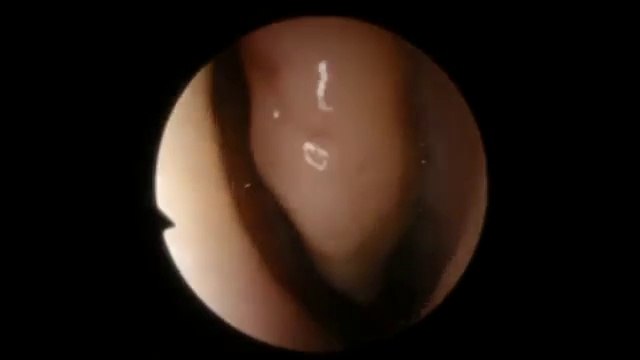

Acute, Sinusitis, Contagious